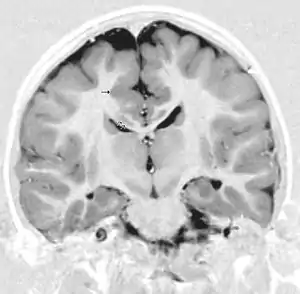

- Radiological findings (MRI) demonstrated symmetric generalized polymicrogyria with decreasing anterior-posterior gradient, most prominent in frontoparietal cortex.[5]

- Numerous gyrus on the cortex

- Small gyri and sulci

- Thin cortex

Neuroimaging The diagnosis of polymicrogyria is typically made by magnetic resonance imaging (MRI) since computed tomography (CT) and other imaging methods generally do not have high enough resolution or adequate contrast to identify the small folds that define the condition. The cerebral cortex often appears abnormally thick as well because the multiple small gyri are fused, infolded, and superimposed in appearance.[5]

Neuropathology Gross neuropathologic examination reveals a pattern of complex convolutions to the cerebral cortex, with miniature gyri fused and superimposed together, often resulting in an irregular brain surface. The cortical ribbon can appear excessively thick as a result of the infolding and fusion of multiple small gyri.[5]